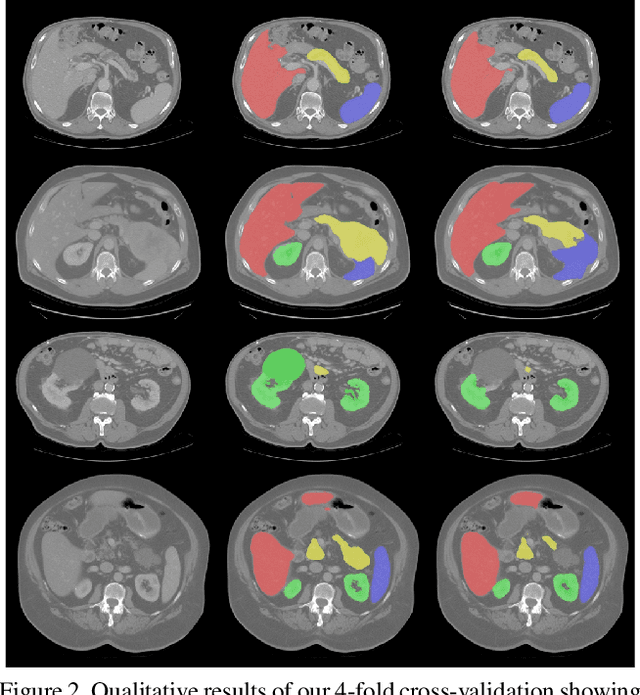

Abstract:As the leading cause of death worldwide, cardiovascular diseases motivate the development of more sophisticated methods to analyze the heart and its substructures from medical images like Computed Tomography (CT) and Magnetic Resonance (MR). Semantic segmentations of important cardiac structures that represent the whole heart are useful to assess patient-specific cardiac morphology and pathology. Furthermore, accurate semantic segmentations can be used to generate cardiac digital twin models which allows e.g. electrophysiological simulation and personalized therapy planning. Even though deep learning-based methods for medical image segmentation achieved great advancements over the last decade, retaining good performance under domain shift -- i.e. when training and test data are sampled from different data distributions -- remains challenging. In order to perform well on domains known at training-time, we employ a (1) balanced joint training approach that utilizes CT and MR data in equal amounts from different source domains. Further, aiming to alleviate domain shift towards domains only encountered at test-time, we rely on (2) strong intensity and spatial augmentation techniques to greatly diversify the available training data. Our proposed whole heart segmentation method, a 5-fold ensemble with our contributions, achieves the best performance for MR data overall and a performance similar to the best performance for CT data when compared to a model trained solely on CT. With 93.33% DSC and 0.8388 mm ASSD for CT and 89.30% DSC and 1.2411 mm ASSD for MR data, our method demonstrates great potential to efficiently obtain accurate semantic segmentations from which patient-specific cardiac twin models can be generated.

Abstract:Even though many semantic segmentation methods exist that are able to perform well on many medical datasets, often, they are not designed for direct use in clinical practice. The two main concerns are generalization to unseen data with a different visual appearance, e.g., images acquired using a different scanner, and efficiency in terms of computation time and required Graphics Processing Unit (GPU) memory. In this work, we employ a multi-organ segmentation model based on the SpatialConfiguration-Net (SCN), which integrates prior knowledge of the spatial configuration among the labelled organs to resolve spurious responses in the network outputs. Furthermore, we modified the architecture of the segmentation model to reduce its memory footprint as much as possible without drastically impacting the quality of the predictions. Lastly, we implemented a minimal inference script for which we optimized both, execution time and required GPU memory.